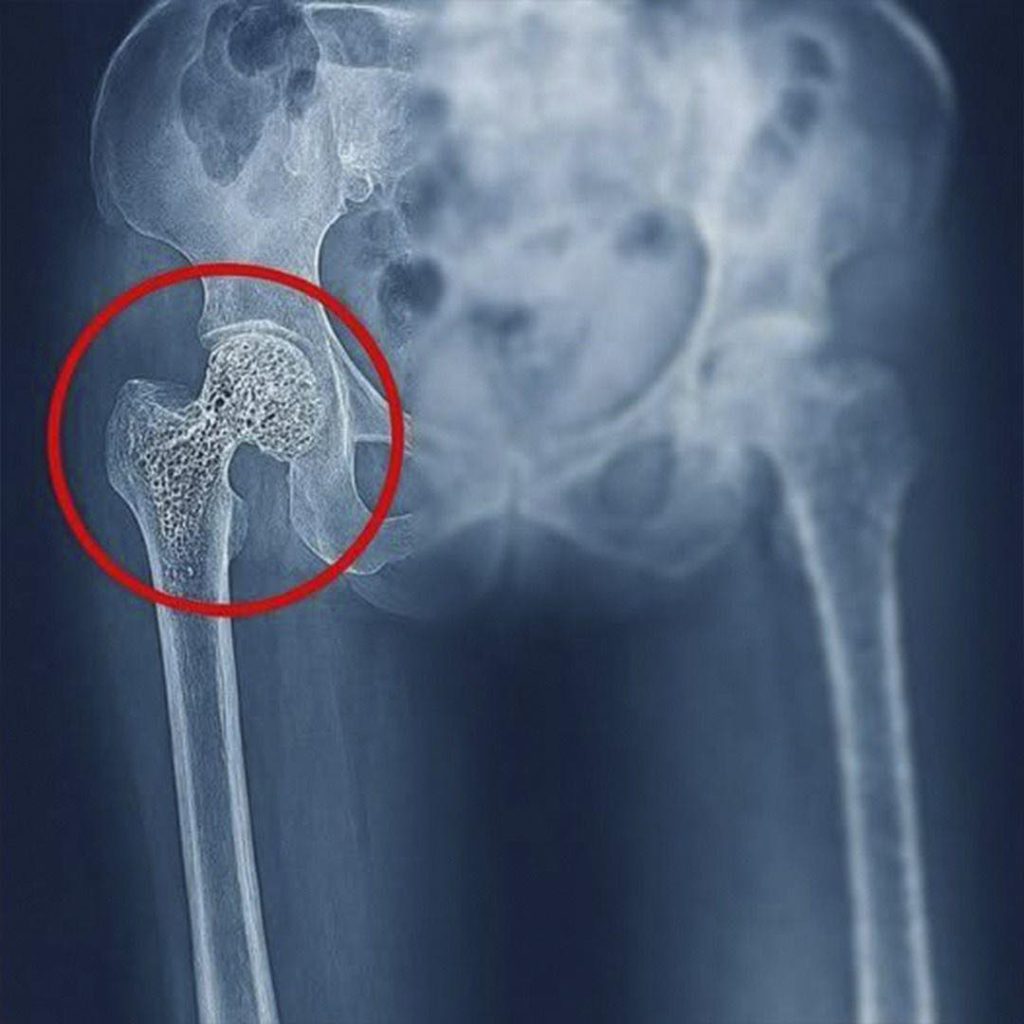

La imagen de una cadera dañada, como la que acompaña esta historia, suele generar un impacto inmediato. No hace falta ser médico para intuir que algo no anda bien. Ese círculo rojo señalando la articulación de la cadera es una alerta visual que resume un problema mucho más grande de lo que parece a simple vista. Detrás de esa imagen hay dolor, limitaciones físicas, miedo al movimiento y, en muchos casos, un cambio radical en la vida de quien lo padece.

La osteoporosis, por ejemplo, es una de las principales causas de fracturas de cadera, especialmente en personas mayores. Se trata de una enfermedad silenciosa que va debilitando los huesos poco a poco, sin síntomas evidentes, hasta que ocurre una fractura ante un movimiento mínimo o una caída leve. En muchos casos, la persona no sabía que tenía los huesos frágiles hasta que ya era demasiado tarde.

Pero no todo problema de cadera es una fractura. También existen afecciones como la artrosis, la necrosis avascular, la bursitis o las lesiones por desgaste. La artrosis, por ejemplo, aparece cuando el cartílago que recubre la articulación se va deteriorando, provocando dolor, rigidez y pérdida de movilidad. Es común en personas que han sometido sus caderas a sobreesfuerzos durante años, ya sea por trabajo físico intenso, deportes de alto impacto o exceso de peso corporal.